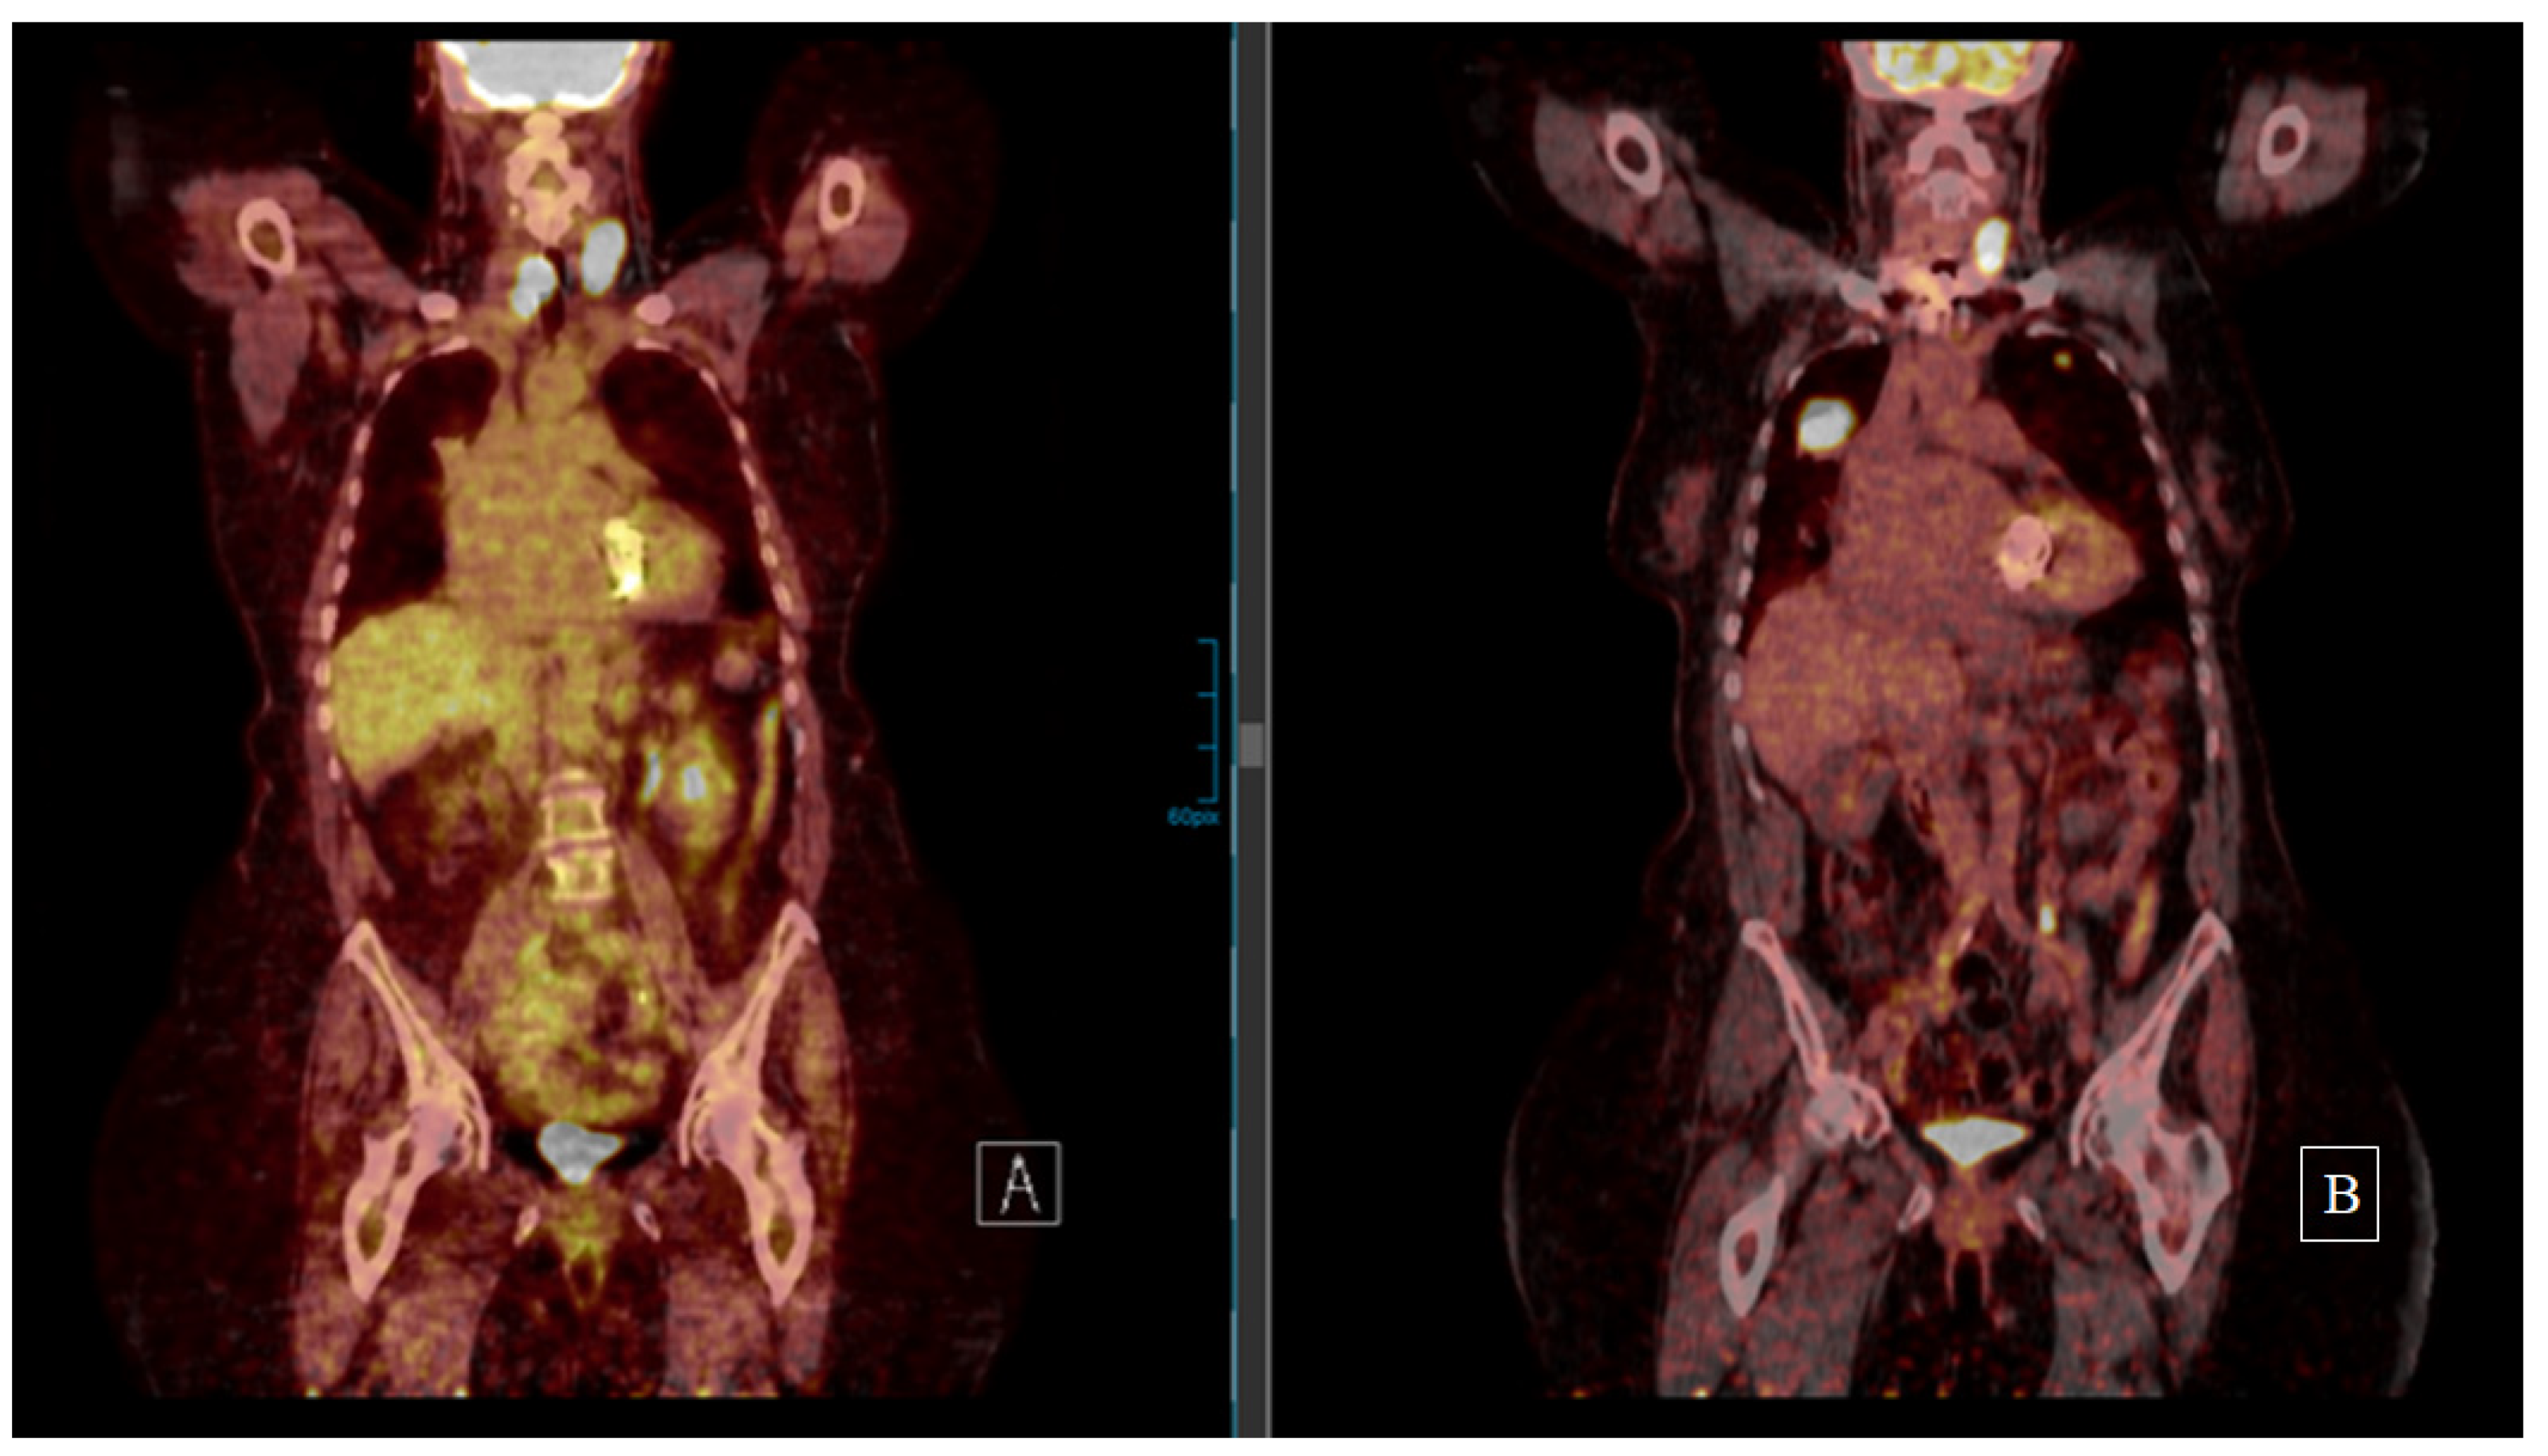

There is one (8.3%) incomplete response (I.R.) with elevated Tg without structural disease, two (16.6%) stable disease (S.D.) cases, whereas all other patients showed slow progress during last follow-up. Patient 4 was lost to follow-up after 6 months. Among the eight (66.7%) patients receiving both surgery and EBRT, only patient 6 and 8 had no further cervical recurrence after the repeated surgical resection. In the other six (75%) cases, the cervical relapse recurred again despite surgery and EBRT (Figure 2).

Figure 2.

Patient 5 underwent resection of a cervical FTC recurrence diagnosed 5 years after thyroidectomy despite bilateral lung metastases (18F-FDG PET on the left side (A)). Cervical and thorax EBRT were performed. The 18F-FDG PET on the right (B) (5 years after the second cervical resection and 10 years after first FTC diagnosis) shows both cervical and lung progress. After thorough patient information concerning the evidence on tyrosine kinase inhibitors, the patient refused treatment and was progressing at last follow-up.